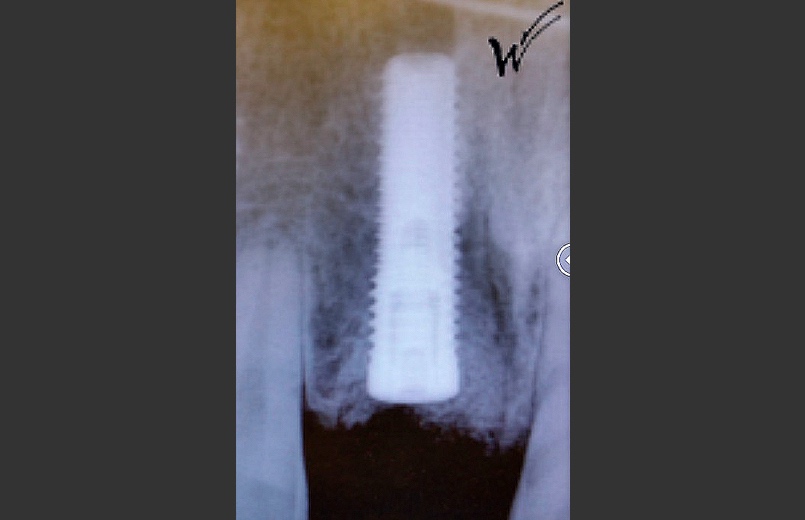

L’implant a été positionné dans l’alvéole, aligné avec la racine. À ce stade, un guide chirurgical peut s’avérer extrêmement utile, en particulier pour éviter d’éventuels obstacles anatomiques, tels que des paquets vasculo-nerveux situés dans le trou rétro-incisif.

Après la guérison des tissus mous (gencive) et durs (os alvéolaire), la couronne céramique esthétique a été installée sur l’implant.

L’implant dentaire peut être posé avant ou pendant la réalisation des greffes osseuses et gingivales, avec l’adjonction de PRP et de PRF. Une option consiste à utiliser une guidance numérique lors de la pose de l’implant. La fabrication d’une couronne céramique cosmétique fixe, qui reconstitue la couronne dentaire naturelle, intervient après l’ostéo-intégration de l’implant dentaire et la maturation des greffes.